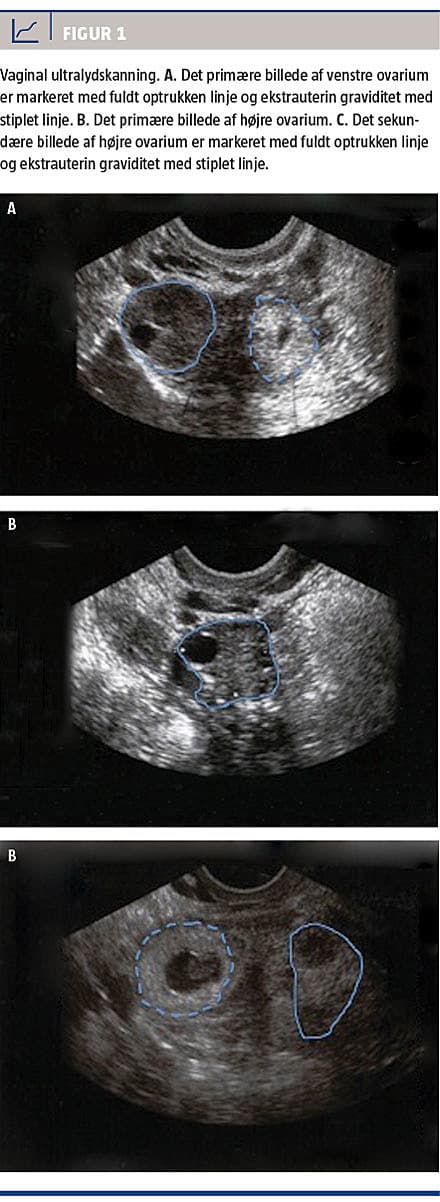

En 33-årig kvinde blev indlagt med vaginal blødning og lette abdominalsmerter. Hun var spontant og ønsket gravid med positiv graviditetstest (urin-humant choriogonadotropin (hCG)) og menostasi igennem fem uger. Hun var i øvrigt sund og rask og havde haft to tidligere fødsler ved kejsersnit fire og ti år tidligere, objektivt var hun upåvirket og hæmodynamisk stabil. Ved en vaginal ultralydskanning fandt man en tom uterus med smalt midtlinjeekko og en mulig proces ved venstre ovarium, højre blev vurderet som normalt uden fri væske. Kvinden blev behandlet som »gravid med ukendt lokalisering« med udvidet genhenvendelsesvarsel og kontrol af S-hCG-niveau.

Hun henvendte sig igen samme aften med tiltagende smerter og et S-hCG-niveau på 2.530 mIU/ml. Ved en ny vaginal ultralydskanning genfandt man den venstresidige proces, der nu var suspekt for EUG (Figur 1A og Figur 1B). Ved en operation blev højre salpinx beskrevet som normal medialt, men lateralt adhærent til ovariet og med ødelagt fimbriaeapparat, men på grund af massive adhærencer kun delvist synlig. Hun blev udskrevet

Kvinden blev genhenvist 23 dage senere. Hun havde været alment utilpas i det meste af den mellemliggende periode med lette abdominalsmerter, men hun var objektivt upåvirket. Der blev foretaget en vaginal ultralydskanning med et karakteristisk fund af en mulig EUG på højre side (Figur 1C), der var ingen fri væske. Ved genindlæggelsen var S-hCG-niveauet på 11.400 mIU/ml. Ved operationen fandt man hele vejen rundt om salpinx talrige adhærencer, der blev løsnet før det endelig fund af en højresidig tubar graviditet. Efter salpingektomien blev S-hCG-niveauet fulgt til 0 mIU/ml, og behandlingen blev afsluttet med videre opfølgning i fertilitetsambulatoriet pga. fortsat graviditetsønske.